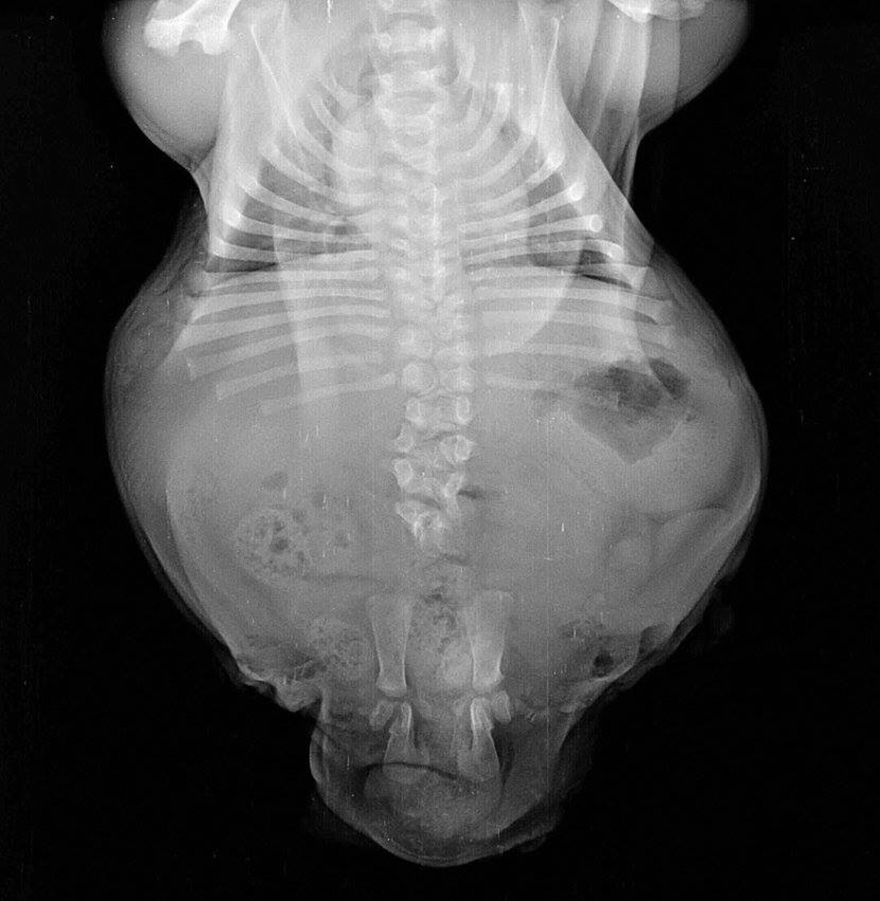

X-rays revealed that he was born with sacs of fluid inside his body

Bonsai’s two stunted, lame hind legs were recently amputated. He also has no functional pelvis and a deformed lower spine. His front legs exhibit legs “Swimmer Puppy” syndrome, which prevents him from standing on his front legs correctly and places excess pressure on his internal organs. This, in turn, might have been caused by the large internal sack of fluid he was born with. He was born to English Bulldog breeders in Arkansas.

He has a short, crooked spine and dysfunctional pelvis

His splayed front legs indicate Swimmer’s Syndrome, which puts excess pressure on his internal organs when he’s upright